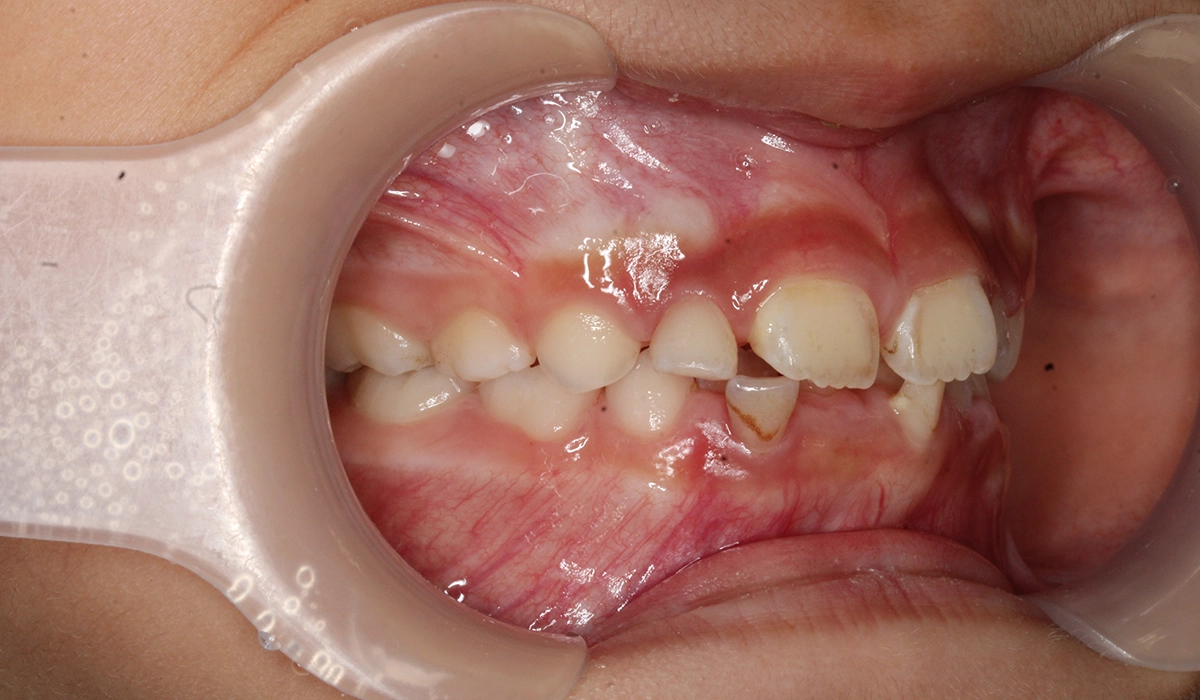

術前:右側

術後:右側